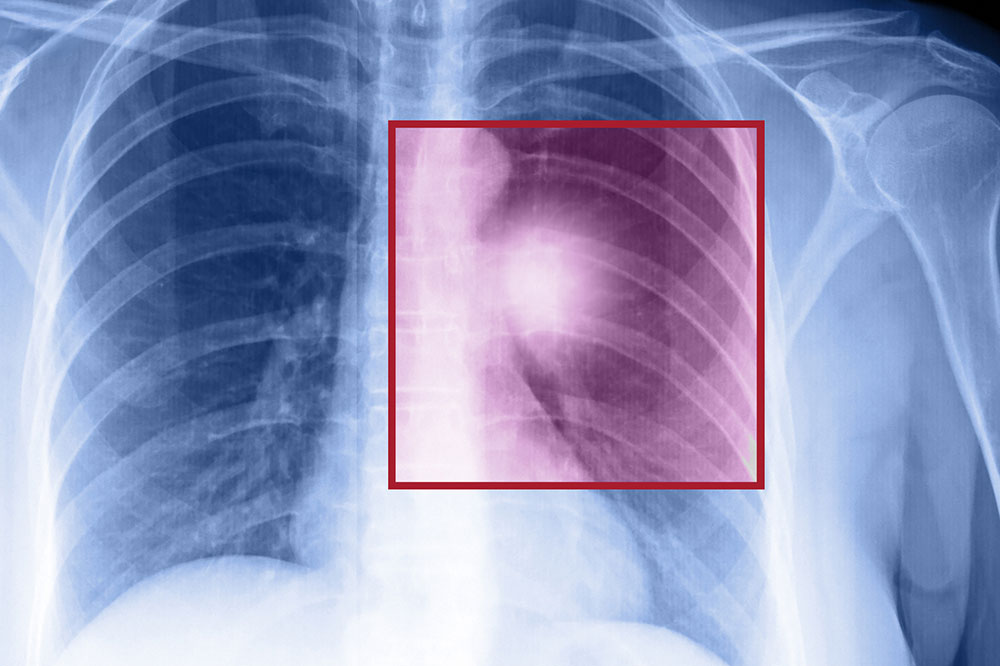

Lung cancer – Types, symptoms, and causes

When the cells in the lungs begin to abnormally multiply and grow, it results in cancer. Lung cancer is one of the leading causes of death in the world. And the risk of suffering from this life-threatening disease is even higher when one is a smoker. Herein, we discuss the various factors that come into play when it comes to lung cancer. Symptoms of lung cancer Usually, lung cancer does not present any symptoms or signs in the early stages. However, as the disease progresses, one may notice Headache Bone pain Loss in weight Hoarse voice Chest pain Shortness of breath Coughing of blood A new cough that persists One should consult a doctor if they notice these signs. If someone is unable to quit smoking, they should visit a medical practitioner for quitting techniques to help avoid this disease. Types of lung cancer There are two kinds of lung cancer: Non-small cell lung cancer This is a catchall term that includes many varieties of this disease, like large cell carcinoma, squamous cell carcinoma, and adenocarcinoma. Small cell lung cancer This happens mainly to people who are heavy smokers, and it’s rarer than non-small cell lung cancer. Risk factors of lung cancer Various factors put you at risk of getting this disease.